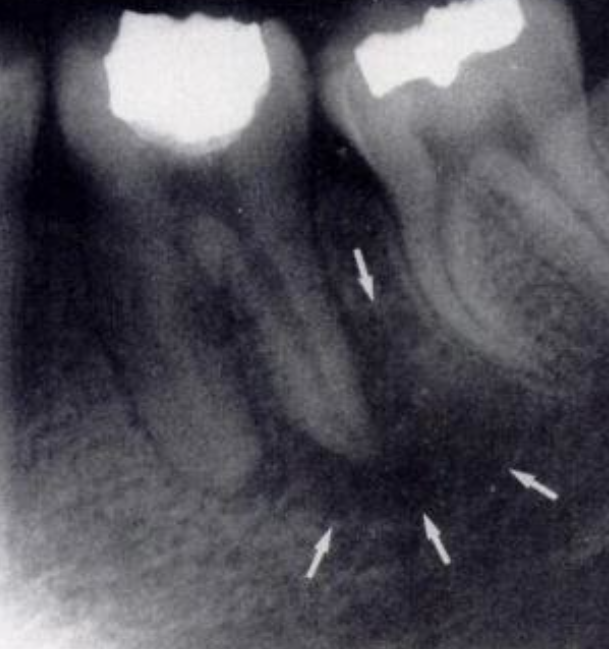

If tooth pain is caused by conditions like caries, pulpitis, or periapical periodontitis, the inflammation may gradually spread. For example, untreated pulpitis can lead to the spread of infection to the periapical tissues, and even affect adjacent teeth through periodontal tissues. This results in symptoms such as pain, sensitivity, or loosening in multiple teeth.

Periodontitis is a common oral disease that can involve the gingiva, alveolar bone, and periodontal ligament of all teeth. When periodontitis worsens in one tooth, it may trigger inflammation of the periodontal tissues throughout the dentition. This leads to general tooth sensitivity and pain, which is particularly noticeable when chewing or coming into contact with hot, cold, sour, or sweet foods.

If pain in one tooth radiates to all teeth, seek medical attention promptly. Determine the cause through oral examinations, X-rays, and other means, and receive targeted treatment. Meanwhile, maintain good oral hygiene habits, undergo regular dental cleanings, and avoid excessive tooth wear to help prevent oral diseases.